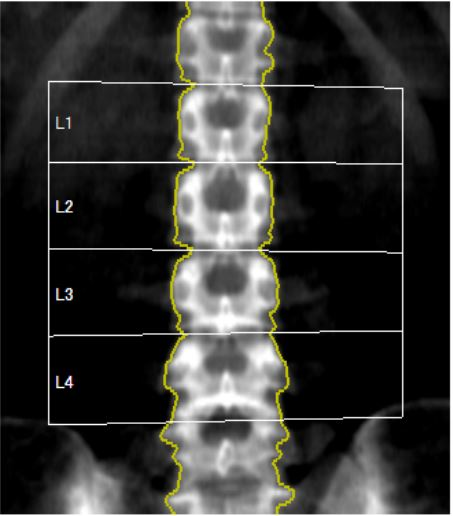

骨密度検査は、骨の強さや密度を測定するための検査です。骨の密度が低くなると、骨がもろくなり、骨折のリスクが高まります。当院では2種類の異なるX線エネルギーを使うDXA法で測定しています。DXA法では高エネルギーと低エネルギーの2つの異なるX線を使い、骨と軟部組織(筋肉や脂肪)の吸収特性の違いを比較し、骨のミネラル密度(BMD)を数値化することで、骨密度の状態を把握します。DXA法の結果は、若年成人(20〜40歳)の骨密度との比較値と同年齢との比較値で表されます。

腰椎の骨密度解析画像 |